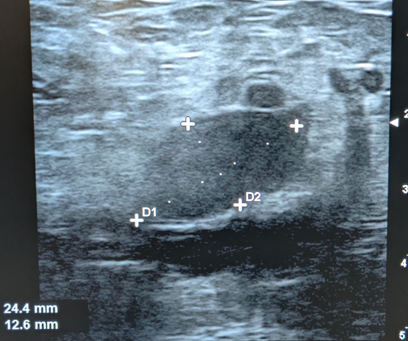

Imagen redondeada hipoecogénica y uniloculada de 25 mm x 12 mm de tamaño. Está conectada con la arteria principal lesionada a través de un cuello (en este caso con la arteria femoral derecha).